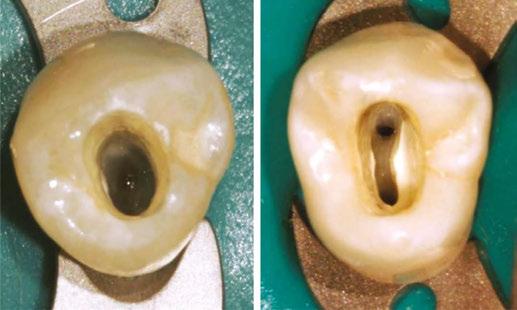

Case 2: This is a 23-year-old male that presented with a constant dull ache in his tooth. Tooth No. 30 tested necrotic with SAP. The CBCT did not reveal any odd anatomy and appeared to be fairly straight forward. After running GentleWave and drying the canals, I injected Endosequence BC Sealer into the ML canal. I could immediately see sealer filling in the MB and then in a mid-mesial canal. The mesial canals were obturated with single cones and the distal using thermomechanical compaction. This case was instrumented using Brasseler Endosequence CM files in the following sequence: 15/.04, 20/.04. The final shift shot radiograph captures the midmesial canal and the split into both the MB/ML